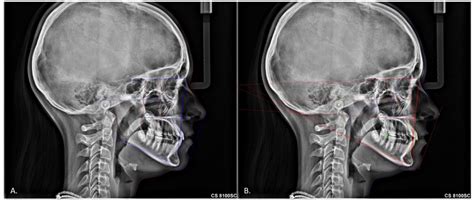

Interpreting Cephalometric X Rays

Interpreting a Cephalometric X Ray requires a thorough understanding of craniofacial anatomy and orthodontic principles. The orthodontist analyzes various landmarks and measurements to assess the patient’s dental and skeletal relationships. Some of the key landmarks and measurements include:

Key Landmarks

The following table outlines some of the key landmarks used in Cephalometric X Ray analysis:

Landmark Description

Sella (S) The center of the sella turcica, a depression in the sphenoid bone

Nasion (N) The most anterior point of the frontal bone at the nasofrontal suture

Orbitale (Or) The lowest point on the inferior margin of the orbit

Pogonion (Pog) The most anterior point on the chin

Gnathion (Gn) The most inferior point on the symphysis menti